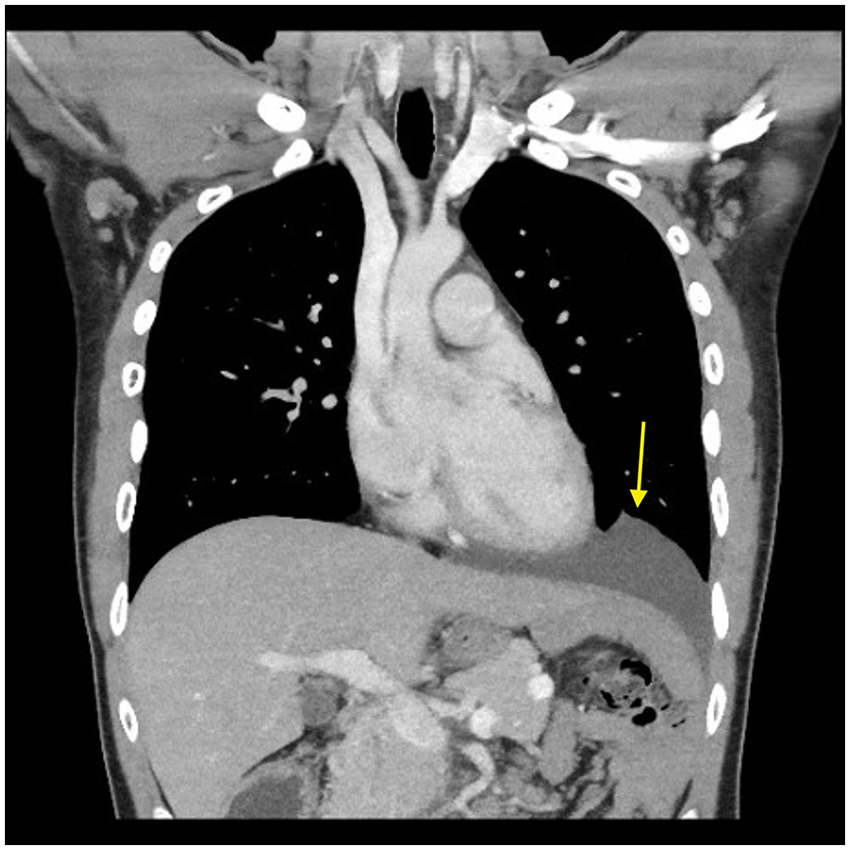

She was hemodynamically stable after receiving analgesics. Physical examination revealed upper abdominal tenderness with no guarding or rigidity, and bowel sounds were hypoactive. Laboratory investigations were unremarkable, with hemoglobin 12.5 g/dL, white blood cell count 9.6 × 109/L, lactate 1.4 mmol/L, amylase 64 U/L, and normal liver enzymes and renal function tests. Cardiac enzymes and electrocardiogram were normal, excluding acute coronary syndrome. Chest x-ray revealed a large left diaphragmatic hernia with evidence of obstruction, demonstrated by herniated small bowel loops with air-fluid levels (Figure 3A). Contrast-enhanced CT revealed a large left diaphragmatic hernia containing a dilated stomach, dilated small bowel loop, and collapsed small bowel loops. Suggesting a strangulated hernia (Figure 3B). Differentiating between partial obstruction and full strangulation was critical for determining the urgency of surgical intervention. Other potential causes of acute upper abdominal pain, such as peptic ulcer disease, acute pancreatitis, cholecystitis, and bowel obstruction unrelated to hernia, were considered but subsequently ruled out based on imaging findings and laboratory results, including unremarkable liver enzymes and amylase levels.

Figure 3. (A) Chest x-ray, PA view. Showing large left diaphragmatic hernia with obstruction, demonstrated by herniated small bowel loops with air-fluid levels (arrows) (B) CT scan of the chest, abdomen, and pelvis with contrast, coronal view. Showing large left diaphragmatic hernia containing a dilated stomach, dilated small bowel loop and collapsed small bowel loops. (L.;liver, P.;pancreas, St.;stomach, Col.;colon, D.S.B; dilated small bowels, C.S.B.; collapsed small bowels).